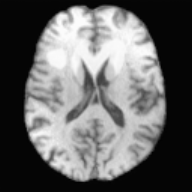

Fig. 3 shows landmark errors in two different regions for the different registration approaches. When registrations are composed through the atlas, errors are much larger than direct longitudinal registration. However, our method shows improvements over cost function masking in both cases. Finally, Fig. 4 shows an example for a brain tumor image. The 3rd column is the predicted quasi-normal image, and the 4th column is the warped image in atlas space. We observe some contrast differences between the tumor and the normal region. However, as our goal is registration, it is not an issue as the correspondences can be established between the reconstructed image and the atlas.

[Uncaptioned image][Uncaptioned image] [Uncaptioned image][Uncaptioned image] [Uncaptioned image][Uncaptioned image] [Uncaptioned image][Uncaptioned image] [Uncaptioned image][Uncaptioned image]

A𝐴A ITsubscript𝐼𝑇I_{T} IRsubscript𝐼𝑅I_{R} IRWsubscript𝐼𝑅𝑊I_{RW} ITWsubscript𝐼𝑇𝑊I_{TW}

Figure 4: One example network result for a brain tumor image. The 5 columns show: 1) the atlas; 2) the tumor image; 3) the reconstructed quasi-normal image, predicted by our network; 4) the warped quasi-normal image; and 5) the warped tumor by applying the transformation.